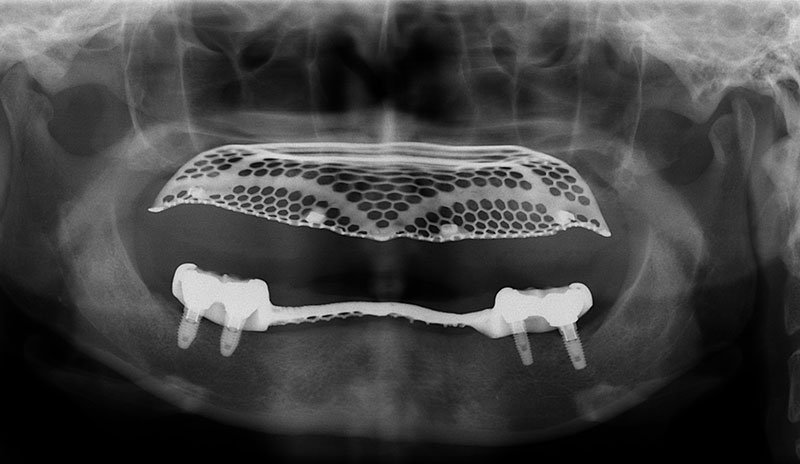

植牙的目的,就是將原來已經失去的咬合能力復原,因此必須更謹慎的評估患者骨質的密度、高度和寬度是否都能滿足植牙的條件。

許多人缺牙多年後才想要植牙,但此時齒槽骨已萎縮,少了堅固的骨頭做為牙根的支撐當然不會穩固。因此可以把補骨想成幫牙根打地基,有了堅硬的地基再植入人工牙根,植牙效果才會穩定耐用。